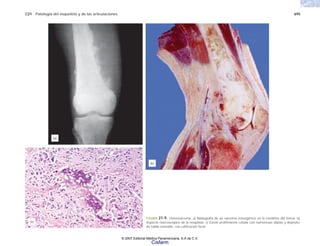

TABLA 8-7

Sitios en donde se pueden efectuar estudios

citológicos.

MICROORGANISMOS PATÓGENOS Y NO PATÓGENOS